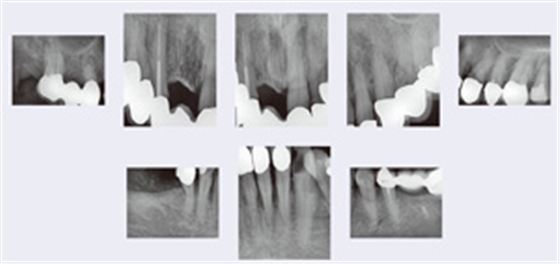

影像檢查

在第一次就診時(shí)患者并沒有帶來她的X 線片。在2013年10 月15 日為其拍攝了8 張X 線片(圖7)。結(jié)果顯示,上頜和下頜的前磨牙和磨牙區(qū)域(不包括37 號牙齒)牙槽骨水平喪失≤25%的牙根長度。上頜前牙及42 號牙齒的水平骨喪失≤50%的牙根長度,而32、31 和41 號牙齒的骨喪失則達(dá)到>50%的根長度。16、14、27 和35 號牙齒顯示根充不完全,35 號牙齒在X 線片上顯示X 線阻射的根充材料只達(dá)到根長度的一半,而16 和14 號牙齒X 線片甚至顯示沒有X 線阻射的根管充填材料,根尖周骨質(zhì)溶解。在36 區(qū)域可以看到一個(gè)無刺激癥狀的殘根。33 號牙齒近中齲壞,43號牙齒近中繼發(fā)齲。下頜前牙區(qū)域可見明顯的牙結(jié)石。

圖7:2013 年10 月15 日的影像學(xué)檢查。